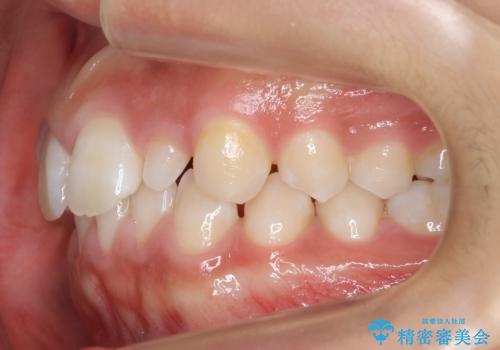

前歯のすきま 矯正治療とセラミックで小さな歯を形良く

- 前歯のすきまを気にして来院。

左上の2番が生まれつき小さく、スペースが余っていました。

右上の2番もやや小さめでしたが、相談の上、左上2番のみセラミックで形を整えることとしました。

そのほかの隙間はマウスピース矯正で閉じることにしました。

当初はワイヤー矯正を希望されていましたが、右上7番の頬側に咬頭があり、ブラケットを貼ることが難しいため、こちらからマウスピース矯正をお勧めしました。